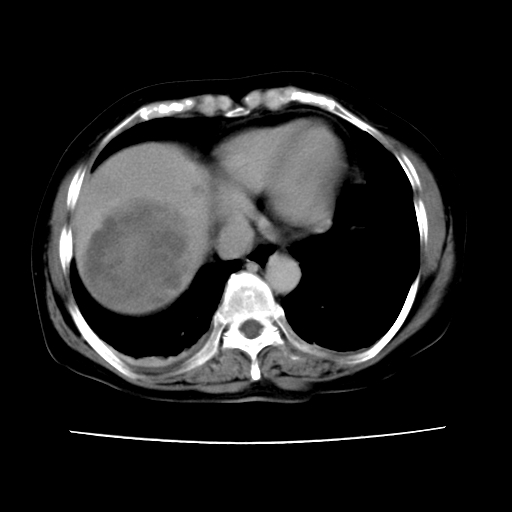

2008-6-10ct平扫

ct增强

6月片:肝血管瘤并破裂出血?肝左外叶囊肿

考虑肝腺瘤出血可能,肝血管瘤增强表现不是很典型,放在第二。

考虑为肝血管瘤破裂出血并肝包膜下血肿;右侧少量胸腔积液。

6月份ct片显示肝内巨大混杂密度团块,伴包膜下积液(内含液液平面),增强多无明显强化。只能考虑肝占位病变,并肝内、血膜下血肿。肝ca并出血多见,而肝血管瘤并破裂出血少见。